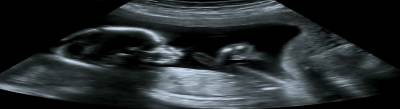

Fetal ultrasounds offer expecting parents the ability to scan their unborn child for any sort of abnormalities. As a noninvasive and painless procedure, ultrasounds are incredibly useful tools for ensuring the health of a fetus from an early stage. There are varying degrees of ultrasounds that are performed, each having its own functionality throughout the pregnancy period. Essays on healthcare, nursing and scientific procedures are only of the few of the many subjects offered in the writing services provided by Ultius.

Expectant parents are anxious to find out about their baby’s health as it grows in its mother’s womb. Fetal ultrasound is a constantly progressing healthcare technology that allows mothers and fathers a window into their baby’s world. Currently, the number of women who request ultrasounds early in their pregnancies are increasing. Ultrasounds in the first trimester provide comfort and reassurance to the expectant mother. Overall, ultrasounds allow the health care provider to evaluate a fetus’s gender, growth, and development. In addition, many expectant mothers realize that ultrasounds allow their doctors to predict their due date. An accurate due date allows the mother to plan her pregnancy and prepare for her baby’s arrival. However, from the health care providers’ perspectives, first and second trimester ultrasounds allow them to determine the growing fetus’s condition and progress, so an ultrasound is an invaluable procedure when assessing fetus development.

Ultrasounds are a routine examination in every pregnancy and can be used in the first or second trimester. Trimesters are differentiated by weeks. The first trimester is usually categorized as up to 13 + 6 weeks, whereas the second trimester is typically 13 to 27 weeks. Health care providers may recommend additional ultrasounds for the pregnancy’s duration, but patients should know that they are straightforward and painless procedures. Essentially, its main task is that it:

In the case of a pregnancy, the obstetric ultrasound takes a picture of the fetus in the woman’s uterus. An ultrasound is either performed over the lower abdominal region or transvaginal, with the transabdominal as the most common procedure for pregnancies. In both scenarios, the expectant mother may experience slight discomfort due the application of a water-based gel or by the insert of the transvaginal transducer, but she will not experience any pain.

The images are real time so expectant mothers can watch the baby’s movements and see and hear its heartbeat. As sonographers or health care providers deliver explanations to the expectant parents, they are also taking note of any fetal anomalies. Sonographers and doctors characterize fetal anomalies as major or minor. Minor anomalies are usually not life-threatening; however, major anomalies will affect the fetus’s viability. Ultrasounds can also provide evidence of substance related fetal anomalies. Gliozheni et al. reveals that

A baby’s development is usually a large concern for the expectant mother, so an ultrasound allows her to see her baby’s development. While some of the fetus’s features may be unclear to the untrained eye, doctors or sonographers can explain what the expectant mother is viewing as they perform the ultrasound.